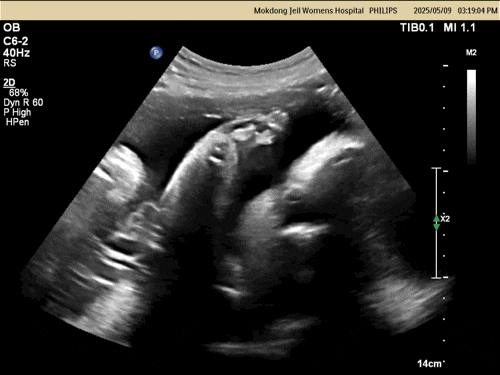

2025.05.06(34주) 갑자기 하루 종일 배가 아팠다. 또다시 변비가 시작된 것 같다.. 2주 정도 마그밀을 먹지...